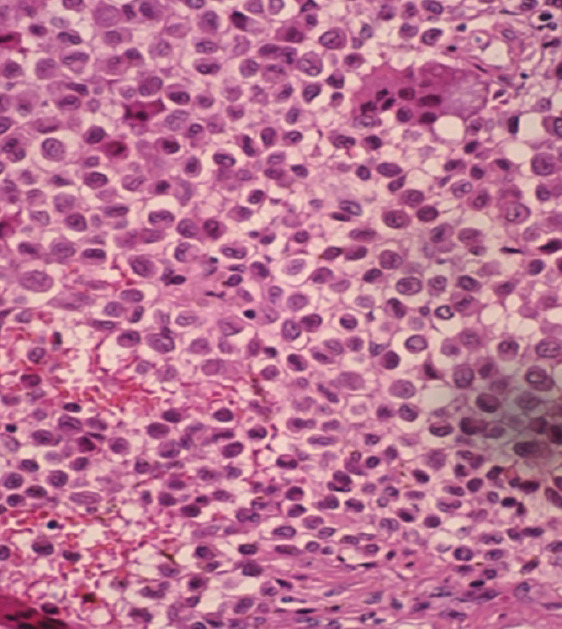

Case report: A 15-year-old female presented with progressive right knee pain of 6 months' duration, worsened by weight-bearing and minimally relieved by analgesics. Clinical examination revealed tenderness and immobile swelling in the region of the medial femoral condyle. Imaging showed characteristic "chicken-wire" calcification, and computed tomography-guided biopsy confirmed chondroblastoma. The patient underwent extended curettage, iliac crest bone grafting, and the use of synthetic bone substitutes. Post-operative rehabilitation showed a good recovery in range of motion and limb function, with no recurrence at follow-up.